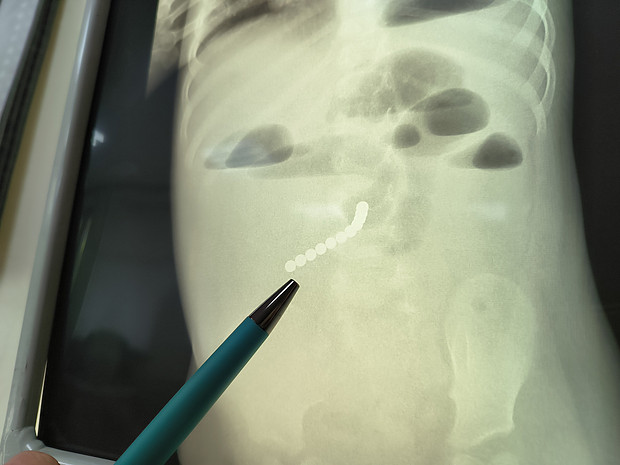

В Кировскую областную детскую клиническую больницу был госпитализирован полуторогодовалый мальчик с вздутием живота и рвотой. На момент поступления у него уже были исключены инфекционные заболевания. Врачи Детской областной больницы незамедлительно начали обследование ребенка и выявили наличие небольших круглых шариков в кишечнике. Маленький пациент отправился на операцию.

– Во время оперативного вмешательства мы увидели в области кишечника инфильтрат – участок ткани с увеличенным объемом и повышенной плотностью. Стали его разбирать, в результате чего обнаружили некое уплотнение между петлей кишки, в которую завернулся весь тонкий кишечник. Именно в этом уплотнении мы и нашли цепочку из магнитных шариков, причем она была там уже давно. Петли кишечника у ребенка были соединены плотной трубкой, в которой находился браслет. Все это вызвало опасное для жизни малыша состояние, – рассказал врач-хирург Кировской областной детской клинической больницы Эдуард Сырчин.

Врачами была проведена ювелирная операция, в рамках которой маленькому пациенту устранили заворот кишок, достали магниты, ушили образовавшиеся свищи. Сейчас пациент находится в удовлетворительном состоянии. Специалисты детской областной больницы еще раз напоминают о правилах безопасности, которые должен соблюдать каждый родитель, чтобы сохранить здоровье и жизнь своего ребенка.